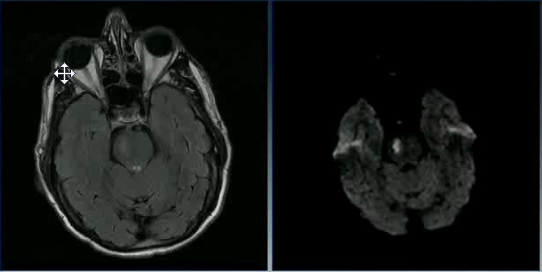

A 20 year old man tries to commit suicide by hanging himself. He is cut down after several minutes and is pulseless. He is resuscitated and regains a heartbeat and respiratory drive and cough to suctioning. Three days later, his exam has not changed. His MRI is attached.

What is the etiology of his brain injury?

Global hypoxia due to asphyxiation and compression of all four major vessels to the brain.

What areas or layers of the cerebrum are affected?

Lamina 3-5 of the entire cerebrum. These lamina are particularly sensitive to hypoxia and die earlier than other areas of the brain.

Case 2 Q# 3 of 4

Why are the ventricles and sulci barely visible in the MRI?

The ventricles and sulci have been compressed by widespread cortical edema

9

Case 2 Q# 4 of 4

When must this MRI have been taken? Why?

The MRI must have been taken a few days after the injury; cortical edema takes days to show up. Glial cells and astrocytes are able to survive longer (20-30min) during ischemia than neurons (6-10min); their (proportionately greater) survival kept most of the brain’s structure intact despite widespread neuronal death.